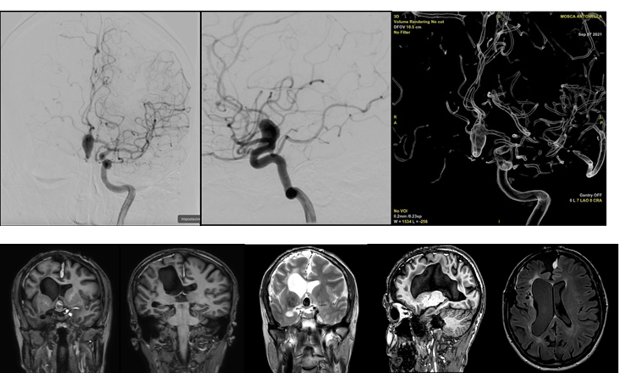

Linear Scleroderma “En Coup de Sabre” with Neurological Manifestations and Neurovascular Abnormalities: A Case Report

1. Abstract Localized scleroderma (LoS) is distinct from systemic sclerosis due to the lack of visceral involvement: among its subtypes, linear scleroderma “en coup de sabre” (LScs) has been associated